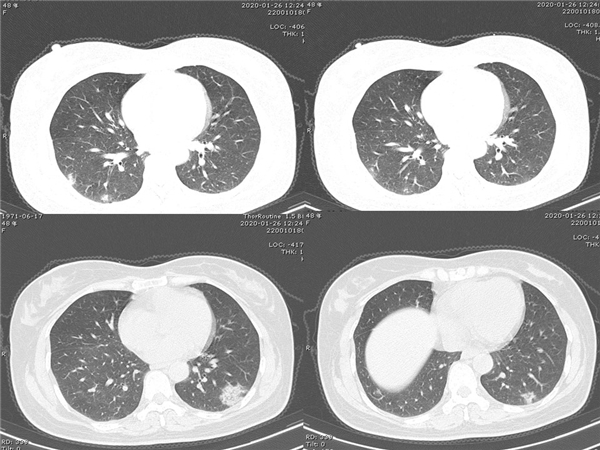

【病例分享】新型冠狀病毒感染肺部CT影像4例(常德市第一人民醫(yī)院)